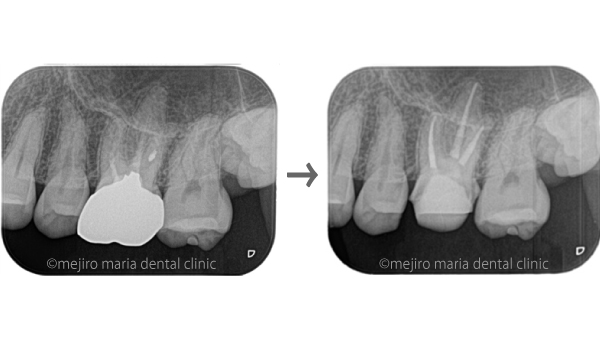

当院での初診時の検査でレントゲンを確認すると、歯冠(歯肉の上に出ている歯の部分)に人工的な透過像が確認でき、前医での治療の際に、偶発的に歯に穴(穿孔・パーフォレーション)が開けられてしまったことが予想できました。また、歯肉(歯ぐき)が大きく腫れあがり、限局的な歯周ポケットが確認される上に、穴のあいている部分と歯周ポケットが交通している可能性も考えられるなど、状況は複雑化していました。

今回は根管形態が複雑ではなかったため、初回で根管内をすべて洗浄後、根管充填と穿孔修復(パーフォレーションリペア)を行い、2回目の治療にて、歯の土台を作る支台築造処置を終了させました。

根管治療終了1ヶ月後に経過観察を行い、術前に確認されていた限局的な歯周ポケットは正常範囲まで回復したのを確認しました。2ヶ月後にはレントゲンにて歯の根の先に見られた黒い透過像の縮小も確認できたため、仮歯を作製し、問題がなければ最終補綴に移行する予定です。